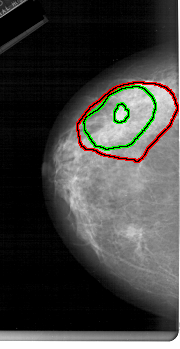

FILE: A_1233_1.LEFT_CC.OVERLAY

TOTAL_ABNORMALITIES 2

ABNORMALITY 2

LESION_TYPE MASS SHAPE IRREGULAR MARGINS SPICULATED

ASSESSMENT 5

SUBTLETY 4

PATHOLOGY MALIGNANT

TOTAL_OUTLINES 2

BOUNDARY

CORE